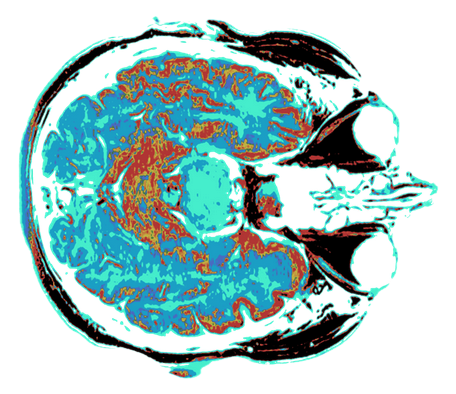

Wolfram commence par poser la question de savoir ce qui se passerait si les cerveaux humains étaient plus grands, en nombre de neurones et de connexions. Il note que la taille actuelle du cerveau humain (environ 100 milliards de neurones) permet la capacité de langage, la pensée complexe et la prise de décision. Mais que se passerait-il si notre cerveau était cent fois plus grand ou plus complexe ?